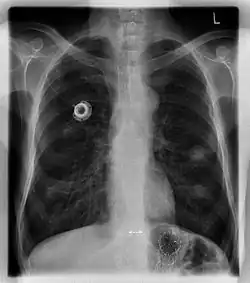

The port is usually inserted in the upper chest (known as a "chest port"), just below the clavicle or collar bone, with the catheter inserted into the jugular vein.

A port consists of a reservoir compartment (the portal) that has a silicone bubble for needle insertion (the septum), with an attached plastic tube (the catheter). The device is surgically inserted under the skin in the upper chest or in the arm and appears as a bump under the skin. It requires no special maintenance other than occasional flushing to keep clear. It is completely internal so swimming and bathing are not a problem. The catheter runs from the portal and is surgically inserted into a vein (usually the jugular vein or less optimally the subclavian vein). Ideally, the catheter terminates in the superior vena cava or the right atrium. This position allows infused agents to be spread throughout the body quickly and efficiently.

Ports can be put in the upper chest or arm. The exact positioning itself is variable as it can be inserted to avoid visibility when wearing low cut shirts, and to avoid excess contact due to a backpack or bra strap. The most common placement is on the upper right portion of the chest, with the catheter itself looping through the right jugular vein, and down towards the patient's heart.